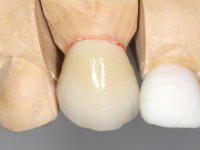

O tratamento iniciou-se com a re -preparação do coto do espigão falso coto fundido, com o objetivo de colocar as linhas de acabamento cervical com uma localização intra-sulcular e simultaneamente confecionar uma coroa provisória adaptada. Com um tratamento ortodôntico muito simples, fechou-se o diastema entre os incisivos centrais superiores e estabilizou-se esta posição com um arame colocado na superfície palatina dos centrais, funcionando como contenção. Posteriormente procurou-se fazer uma tração ortodôntica lenta do dente 2.2 com o intuito de diminuir, ainda que muito ligeiramente a perda óssea vertical nessa zona. Finalizada a tração, foi feita a extração do dente 2.2 e a zona foi reabilitada provisoriamente com uma coroa de resina composta colada aos dentes adjacentes. Foi colocado um implante dentário na zona do dente 2.2 sendo novamente colada a coroa provisória em resina, reabilitando provisoriamente a paciente durante o período de osseointegração. No dente 1.3 foi feita uma gengivectomia com bisturi elétrico, com a intenção de subir o nível cervical do 1.3 conseguindo uma maior harmonia com o dente 2.3. Estabilizados os tecidos moles, foi feita uma impressão com a técnica de moldeira aberta, utilizando silicones de adição de consistência “putty” e “light”. A recolha da cor, tanto da componente dentária como dos tecidos moles foi feita pelo ceramista no consultório.  No laboratório as impressões foram passadas a gesso e deram origem a modelos de trabalho que foram devidamente analisados. Foi decidido confecionar um “abutment” metalo-cerâmico aparafusado sobre o implante. Este “abutment” foi fundido com uma liga nobre e posteriormente revestido a cerâmica coronária e gengival. Dada a inclinação do implante o aparafusamento condicionou de forma inevitável a saída do orifício do parafuso pela superfície vestibular. No sentido de esconder esta situação, o desenho do “abutment” já foi idealizado com a intenção de acomodar na superfície vestibular a colagem de uma faceta feldspática. Este “abutment” foi provado em boca e foram feitos ajustes no componente cerâmico gengival. A sua adaptação aos tecidos moles foi feita tanto de forma subtrativa, com broca, como de forma aditiva, acrescentando resina composta de tonalidade gengival. Este acrescento de resina seria orientador do ceramista na colocação final da cerâmica de tonalidade gengival. A coroa que reabilitaria o dente 1.3 foi cimentada nesta consulta de prova com cimento de ionómero de vidro reforçado com resina composta. Finalizado o trabalho em laboratório da faceta sobre o 1.2 e o “abutment” e a faceta para o implante este foi colado em boca, após a colocação do isolamento absoluto. O trabalho satisfez plenamente a paciente. Durante oito anos a paciente foi seguida regularmente, mostrando-se agradada com o tratamento efetuado, no entanto começou a mostrar interesse em intervir esteticamente nos incisivos centrais superiores. Decidida a segunda fase da nossa intervenção, foi feita a preparação dentária dos dentes 1.1 e 2.1 para a colocação de duas facetas feldspáticas. Particular cuidado foi tido na preparação inter-proximal distal junto ao “abutment” do implante. Foi preciso avaliar muito pormenorizadamente o eixo de inserção da faceta em relação ao “abutment”. As facetas feldspáticas foram confecionadas em laboratório e posteriormente coladas em boca após a colocação de isolamento absoluto. Um ano após, iniciamos a nossa terceira fase de tratamento, após a faceta colada no dente 2.1 ter fraturado. A preparação dentária foi feita sobre a faceta colada, procurando estender mais para palatino o interface inter-proximal distal. O objetivo seria passar para mais palatino do ponto de contacto o interface faceta-dente. O preparo dentário do dente 1.2 também foi muito reduzido, limitando-se a criar um eixo de inserção. Após confecionadas a coroa total e a faceta em laboratório foram coladas em boca. Primeiro foi colada a coroa utilizando-se um isolamento relativo com teflon, posteriormente foi colada a faceta após a colocação do isolamento absoluto. Na coroa utilizei este tipo de isolamento para evitar a utilização de grampos. Seria difícil de aplicar pela forma e dimensão do dente e agressivo para os tecidos moles. Após a colagem foi avaliada a integração oclusal do trabalho.